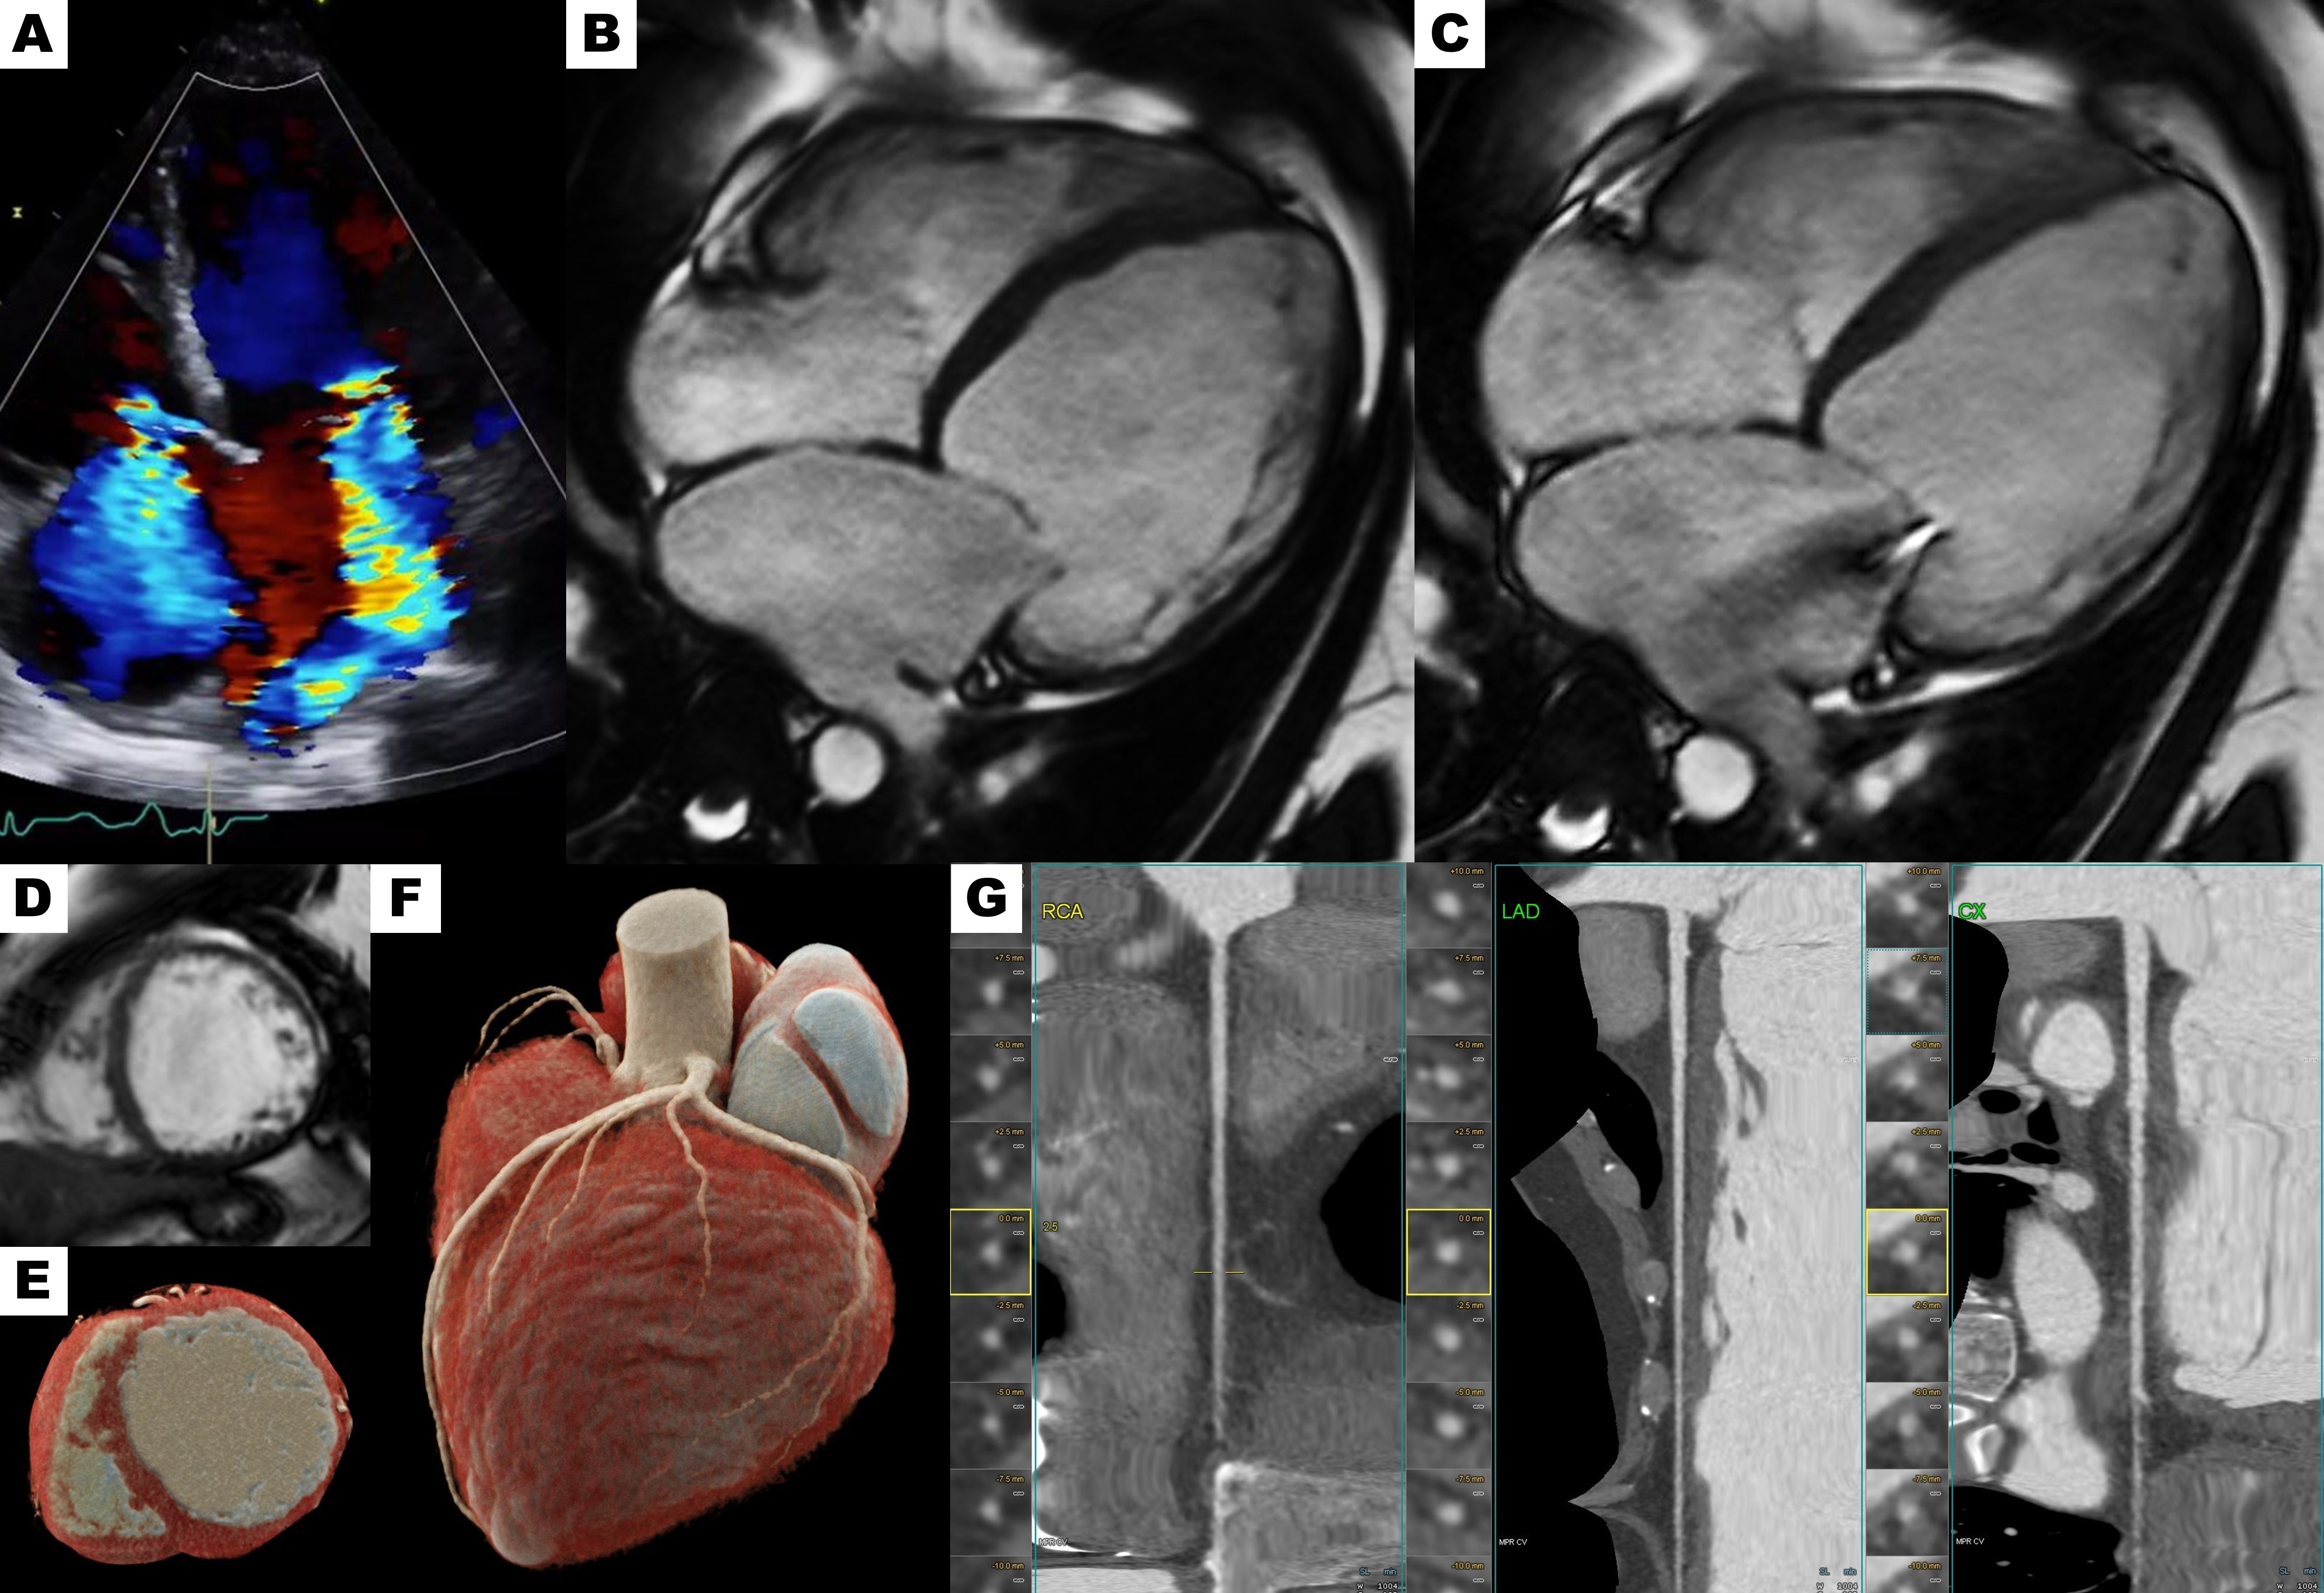

Figure 1. Initial evaluation. (A) Transthoracic echocardiography showing global cardiac chamber dilatation with severe mitral and tricuspid regurgitation. Cardiac magnetic resonance imaging demonstrating chamber dilatation: (B) Four-chamber cine view in diastole, (C) Four-chamber cine view in systole with severe mitral regurgitation, (D) Short-axis cine view. Cardiac computed tomography angiography ruling out coronary artery disease: (E) Short-axis view with biventricular dilatation, (F) Volume rendering technique 3D reconstruction, (G) Curved multiplanar reformation.